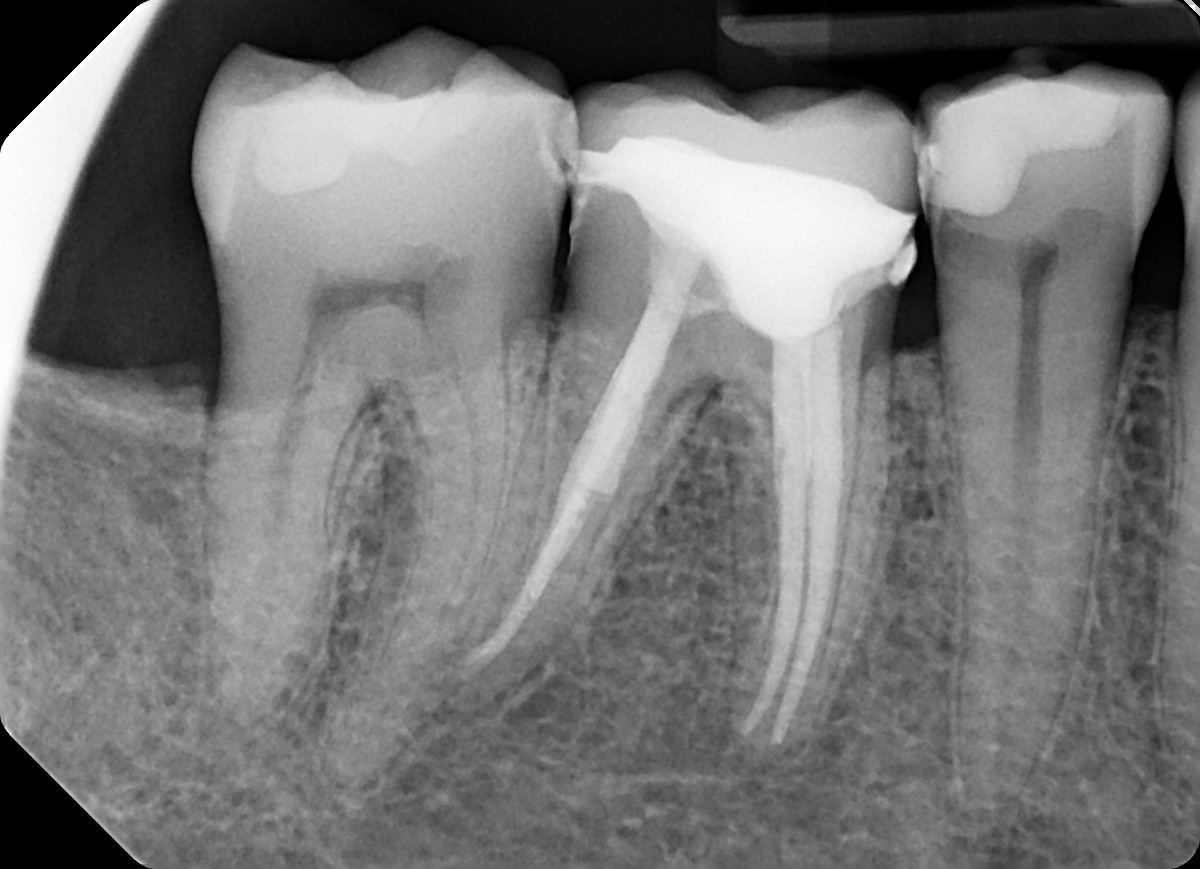

3. What option can explain the crown of the tooth #3.6?